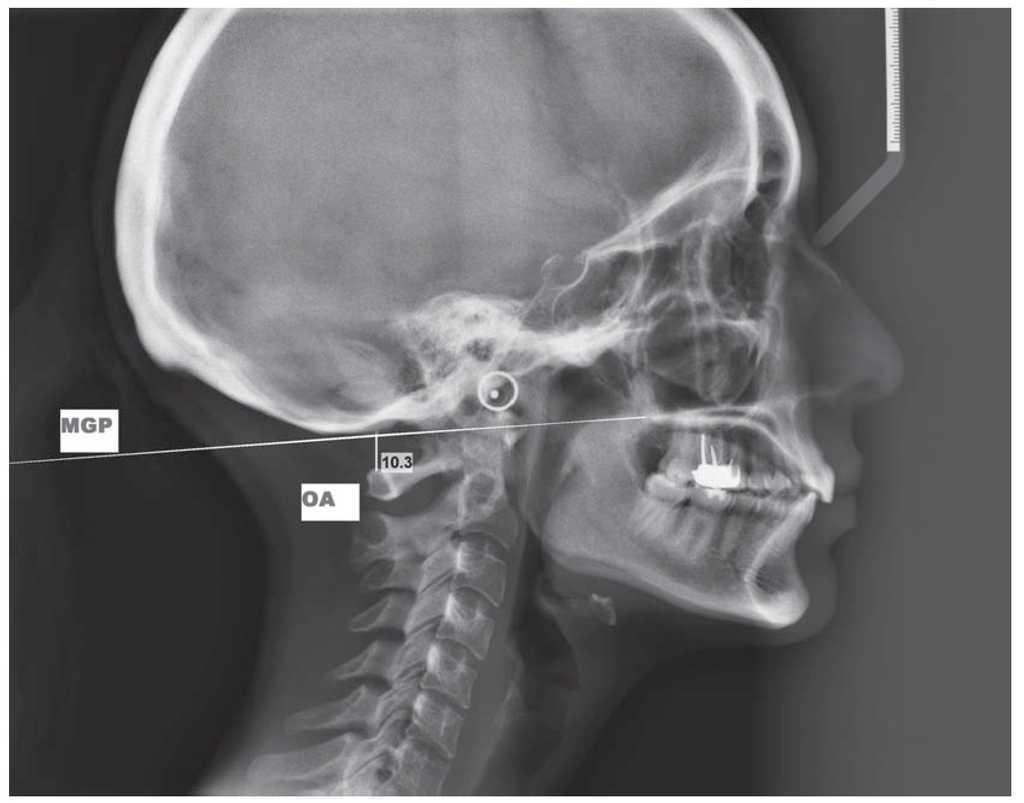

Modificaciones radiológicas del espacio entre el occipucio y el cuerpo del atlas tras una

Estudio comparativo de la posición craneocervical de la cabeza y su relación con patrones